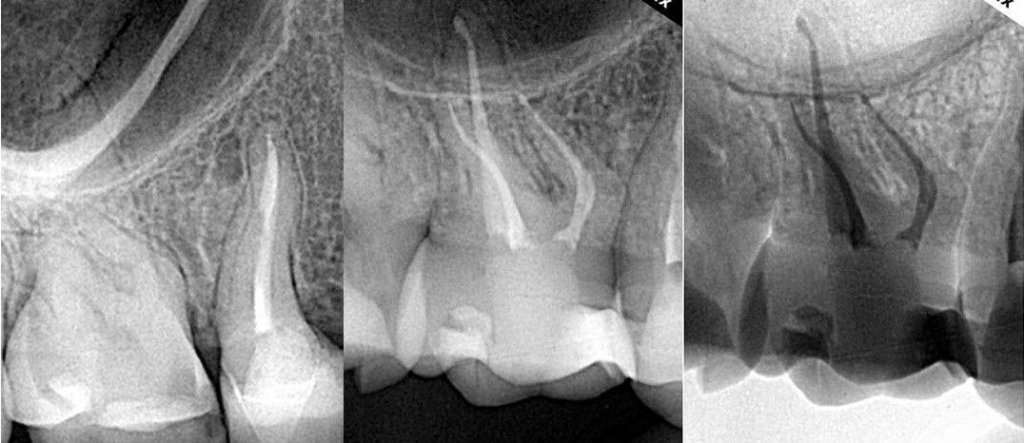

متى أحتاج عالج العصب؟

- ألم شديد في السن

- حساسية قوية من السخونة أو البرودة.

- تسوس عميق وصل للعصب.

- كسر أو خراج (صديد) في السن.